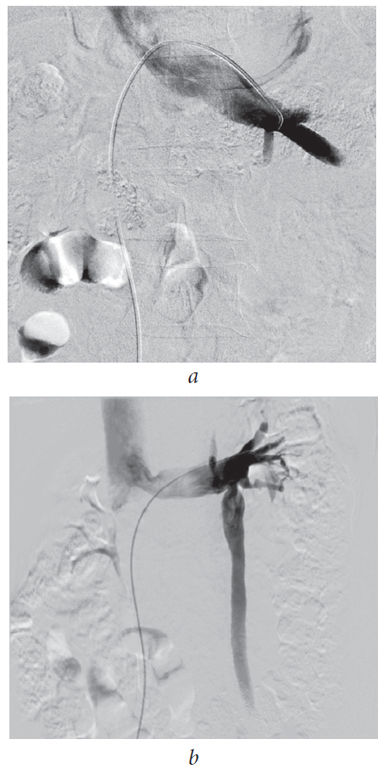

В 2006 г. нами впервые был введен термин «рено-пельвикальный венозный анастомоз» для описания процесса перераспределения венозной крови у больных с левосторонним варикоцеле при артериальном аортомезентериальном пинцете из бассейна левой почечной вены (через венозный анастомотический узел, образованный v. testicularis interna sinistra, v. ductus deferens sinistra и v. cremasterica sinistra) в венозный бассейн v. pudenda interna и plexus venosus prostaticus (рис. 2). Это позволило предположить, что варикоцеле выступает гемодинамической предпосылкой развития венозного полнокровия органов малого таза и рецидивирования хронического простатита (рис. 3) [21].

Рис. 2. Ретроградная флеботестикулография. Рено-пельвикальный венозный анастомоз. Сброс венозной крови в венозное сплетение малого таза по v. ductus deferens sinistra

Fig. 2. Retrograde phlebotesticulography. Renopelvic venous anastomosis. Discharge of venous blood in the pelvic venous plexus via v. ductus deferens sinistra